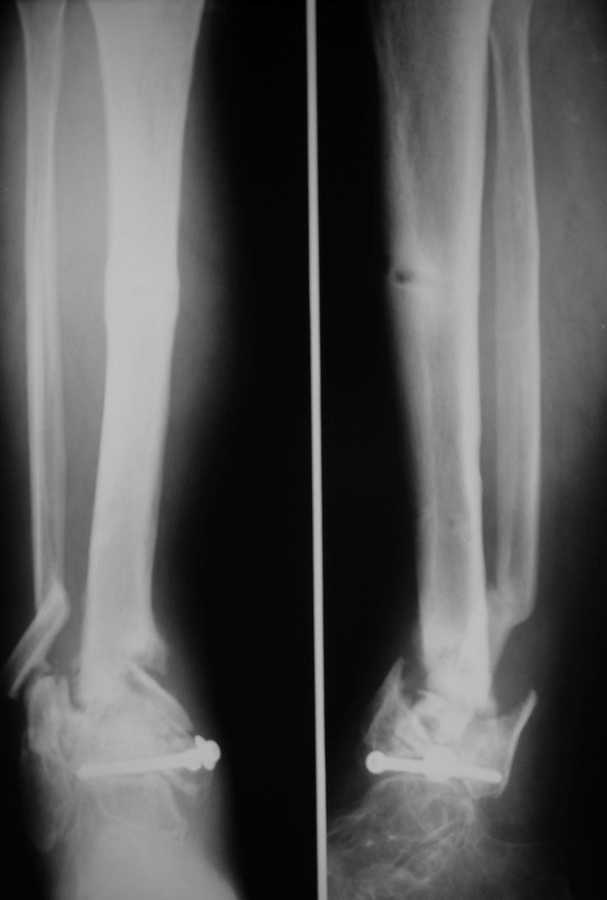

Ложный сустав н/3 голени

Здравствуйте коллеги! К нам поступил пациент 52 лет. Травму получил два года назад,открытый перелом н/3 костей голени.

Со слов больного год лечили аппаратом, винты ввели при ПХО, потом ещё год ходил в гипсовой повязке.Сейчас ложный сустав в н/3, патологическая подвижность при попытке опоры.Наш вариант лечения: резекционная остеотомия малоберцовой, удалить винты,остеосинтез стержнем с рассверливанием и блокированием через пятку, естесственно с артродезом.Кожа чистая, хотя и в рубцах. Или опять аппарат?